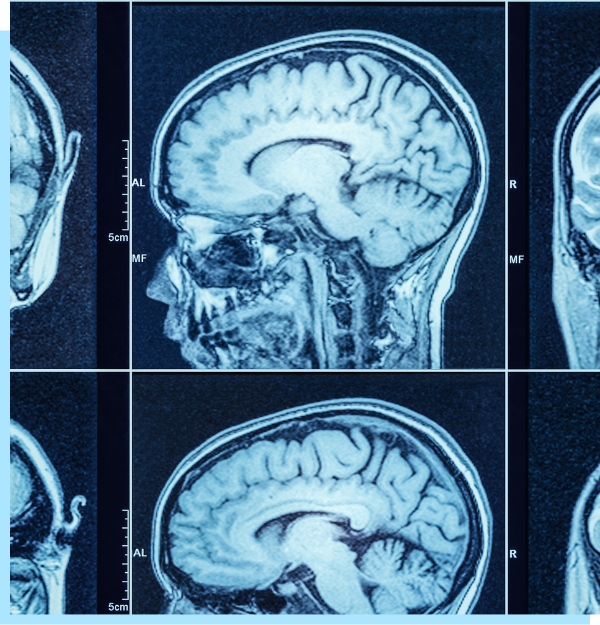

Los estimulantes como la metanfetamina funcionan diciéndole al cerebro que suelte mucha dopamina, un químico que puede hacerte sentir feliz a corto plazo. Pero con el tiempo, la metanfetamina puede agotar el cerebro en áreas importantes que te hacen sentir bien, lo que con el tiempo resulta en depresión y mal humor. La metanfetamina también puede causar problemas cardíacos inmediatamente y otros problemas de salud a través de sus efectos estimulantes en el cuerpo y estos pueden poner en peligro tu vida.